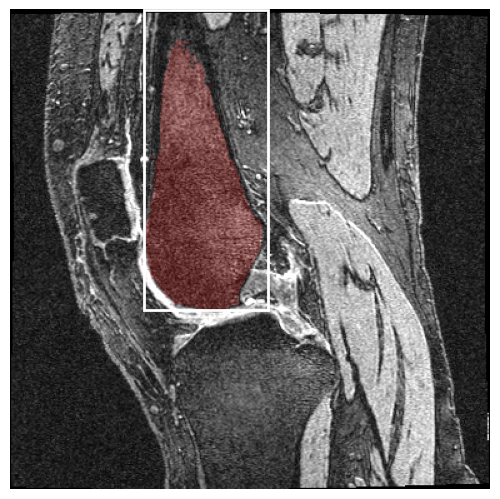

In our work, we extend SAM2 to 3D MRI images by treating slices from 3D volumes as individual video frames. As shown in Figure 1, this method leverages SAM2’s video segmentation capabilities to process 3D data efficiently, enabling precise segmentation of volumetric medical images with minimal user input. This extension significantly enhances SAM2’s performance in medical imaging tasks, achieving higher accuracy and efficiency. Specifically, for zero-shot single-prompt segmentation of knee MRI images, SAM2 achieves accurate results with minimal interaction, thus improving the overall workflow of medical image analysis.

For SAM1, the results showed a general trend in which bounding box prompts outperformed point prompts and larger models performed better. Neither of these results were surprising, especially since bounding boxes provide more information to the model than points. In particular, bounding boxes dictate the size of the object of interest, unlike points. As shown in Figure 2, a common failure case with point prompts was the model’s tendency to select the entire foreground. On the other hand, the positive correlation between model size and DSC was minimal.

For SAM2, the results were more unexpected. Regarding model sizes, the base-plus model was on par with or outperformed the large model, despite having nearly four times fewer parameters. The tiny and small model also had surprisingly high DSC on certain tasks. For the most direct comparison between SAM1 and SAM2, wherein both models used a point prompt for each slice of the MR volume, the DSC scores were about the same. That is, the SAM2 underperformed relative to expectations. When SAM2’s video predictor was activated with the “” prompt scheme, the model boasted its highest and median DSC at 0.9196. Note that the “point” prompt scheme provided two points (femur and tibia) for each slice of the 160-slice volume, resulting in 320 total prompts per volume. Providing only three points proved to be the better option for SAM2. Even the “” prompt scheme with a single prompt per volume gave results on par with that of the “point” prompt scheme.